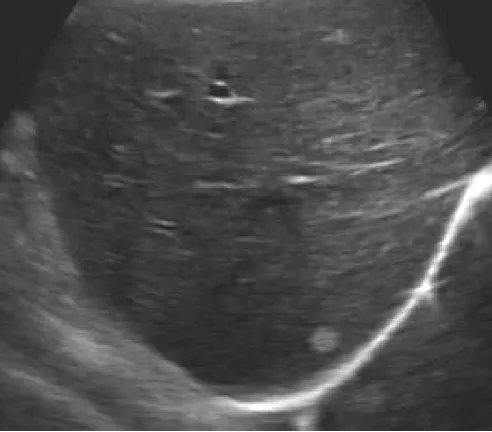

肝血管瘤

● 单发或多发,圆形或椭圆形、边界清晰、回声多样。

● 后方回声可不同程度增强。

● 探头加压可变形、对血管及邻近组织无浸润。

● CDFI:常无明显血流信号,或少量低速血流信号。

(1)高回声型

最多见,小血管瘤(90%)

内部呈筛网状;浮雕样

(2)混合回声型

见于较大的血管瘤

实质呈粗网络状或蜂窝状结构

(3)低回声型

较少见,中等大小的血管瘤

周边回声增强,可见周缘裂隙征